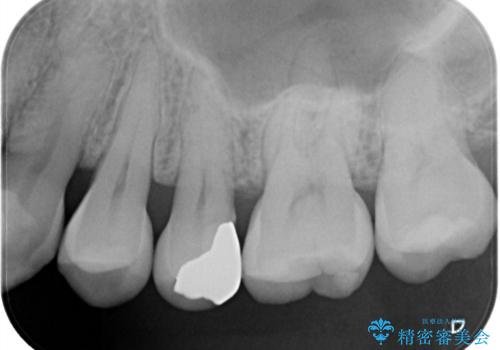

矯正後セラミックインレーにしたい

- 銀歯が気になるためやり替えたいとのことで来院されました。

セラミックインレーで治療を行いました。

口の中にチラつく銀歯は適合の良いセラミックインレーでやり替えることで綺麗にやり替えることができます。